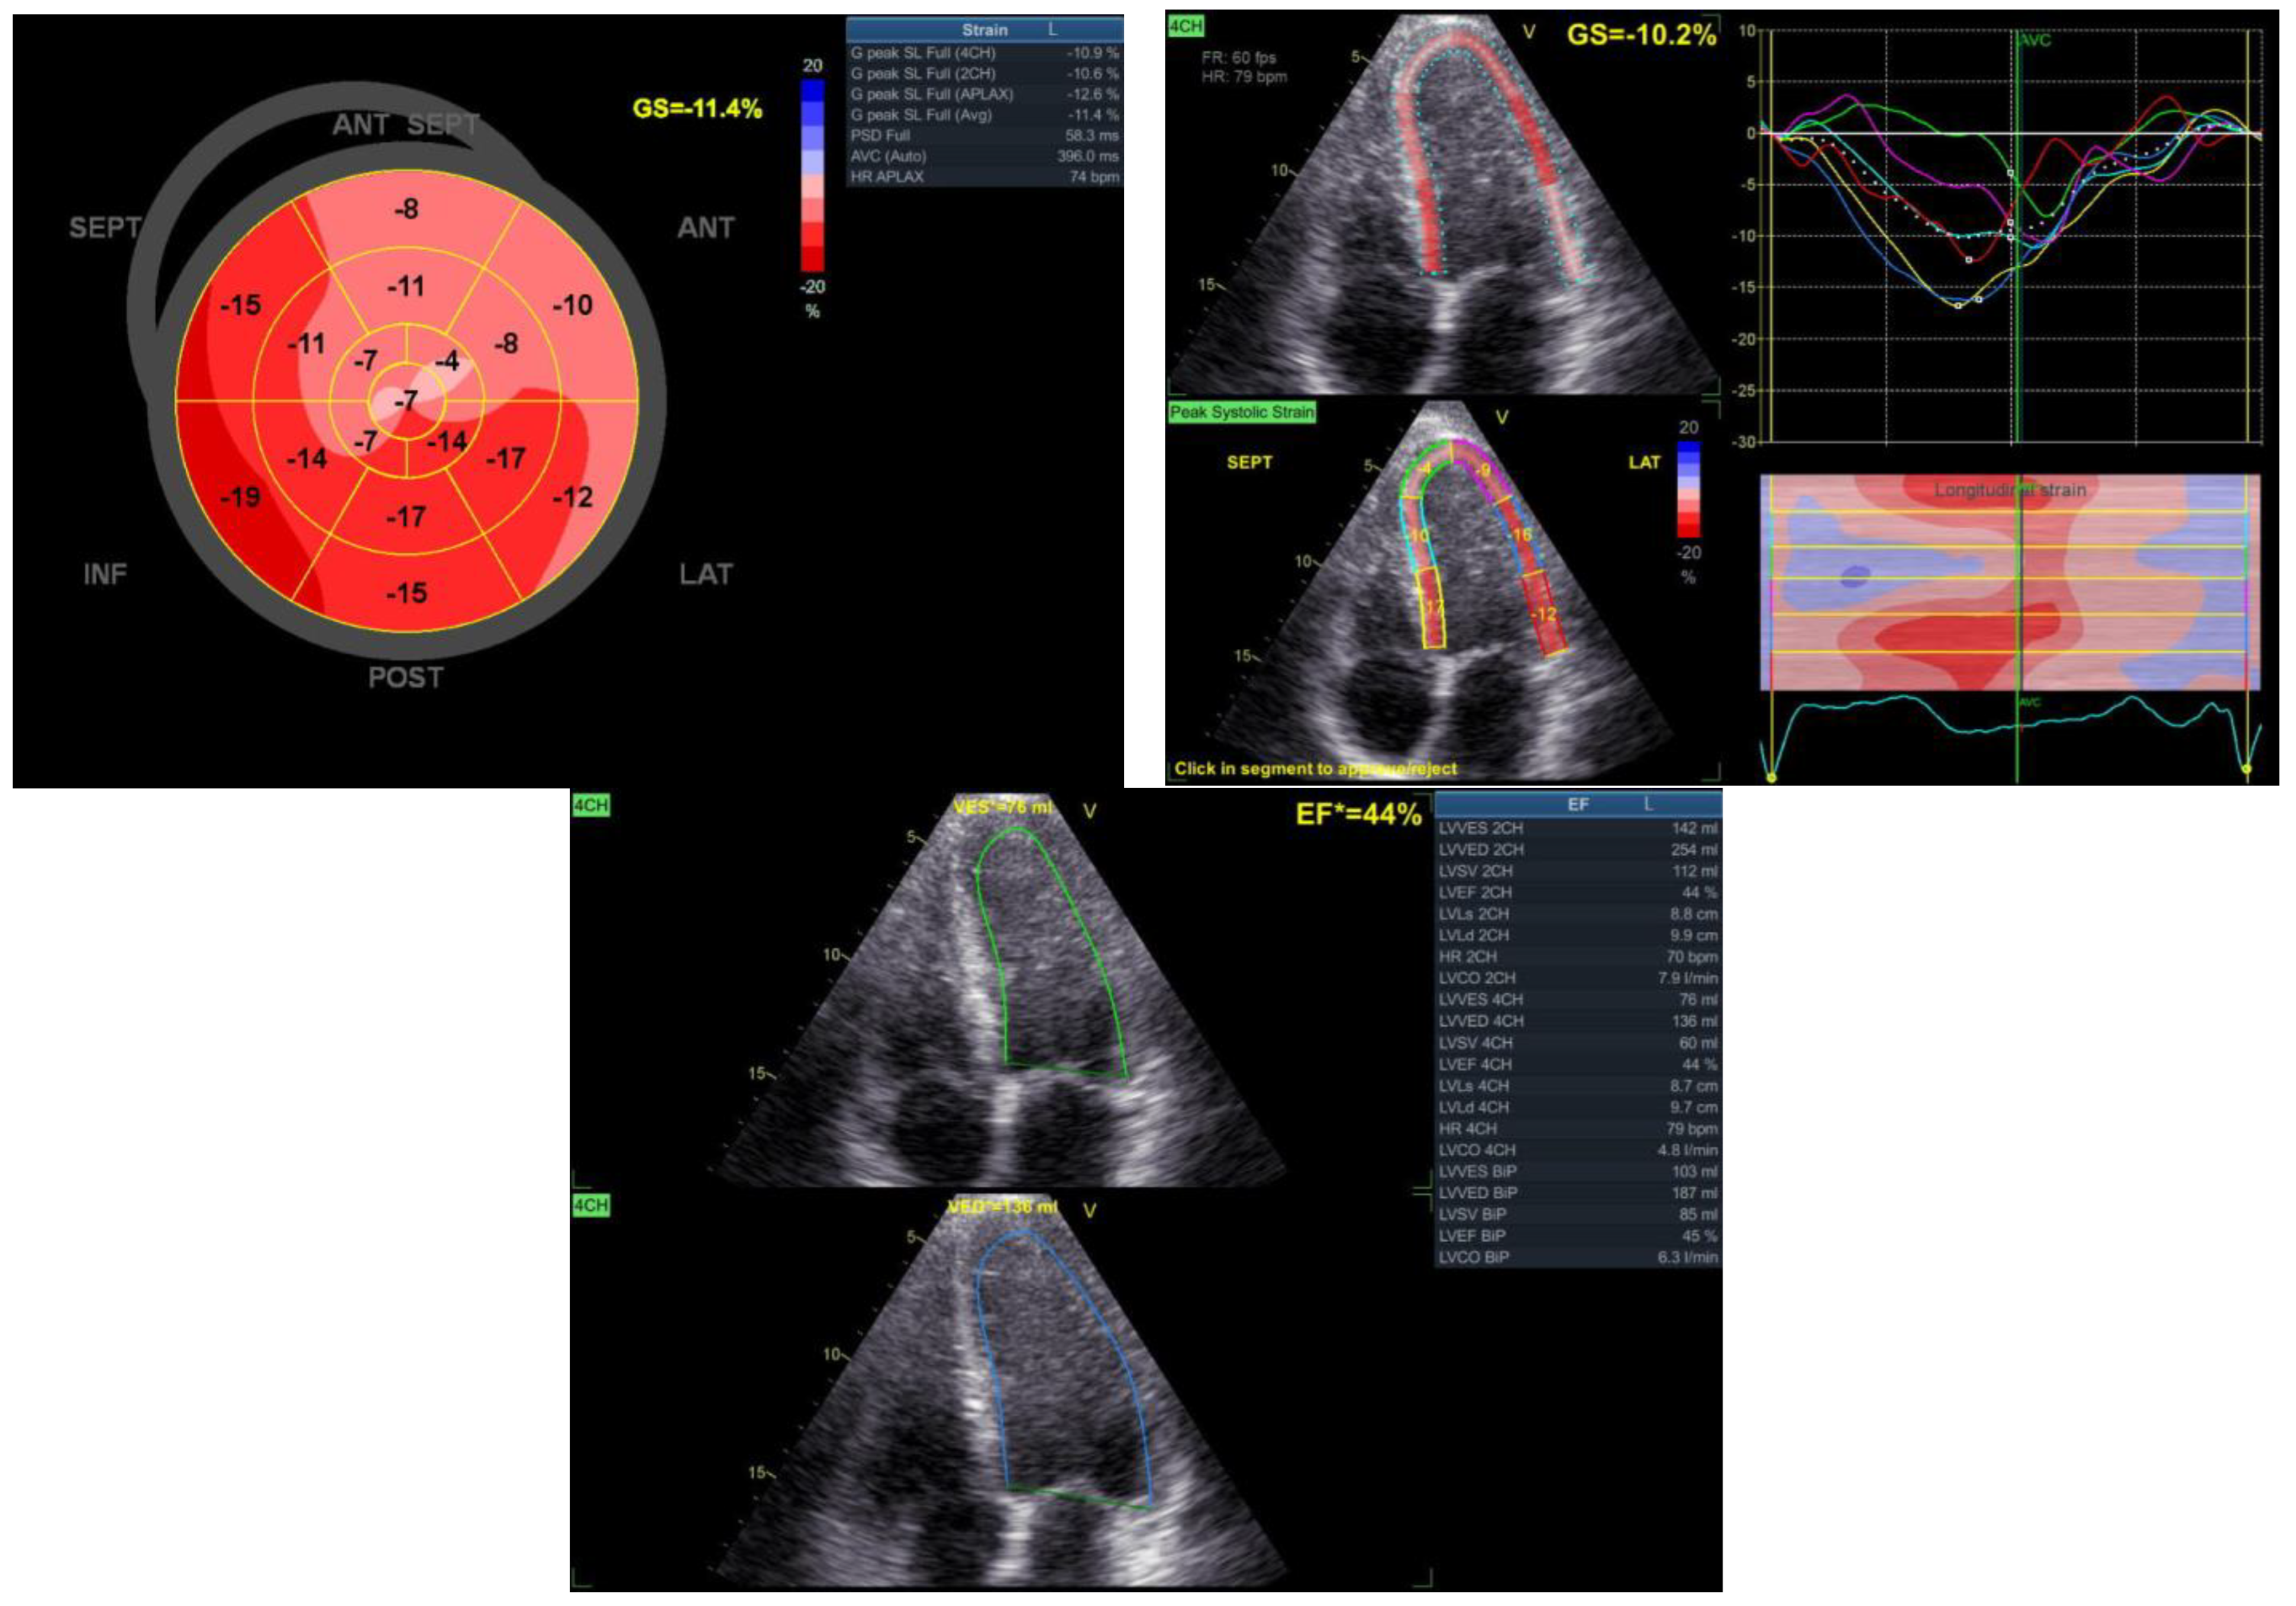

2. Detailed Case Description